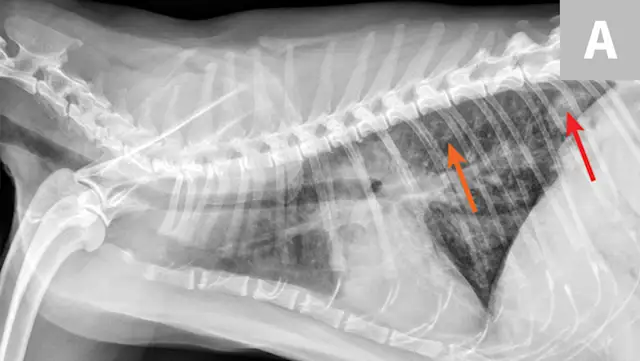

Thoracic radiographs may reveal a bronchointerstitial pattern, alveolar infiltrates, a diffuse bronchial pattern, and (rarely) pleural effusion (Figure 5).10,11 Diagnosis may be made via identification of first-stage larvae from airway cytology specimens or fecal samples. In clinical practice, false-negative fecal samples have been appreciated due to intermittent fecal shedding. Repeated testing may increase sensitivity but has not been evaluated. Therefore, any patient suspected of potential lungworm should be treated. Less common lungworms have been reported in cats, including Paragonimus spp12-14 and Capillaria spp.15

FIGURE 5A

Radiograph of aelurostrongylus abstrusus infection (lungworm). Note the diffuse bronchial pattern (orange arrows), patchy poorly defined soft-tissue nodules (red arrows), and right middle lung lobe alveolar disease (yellow arrow). This pattern could be confused with feline asthma in this case; however, the right middle lung does not appear atelectatic but instead infiltrated. Fine-needle aspiration of the right middle lung lobe confirmed larvae.